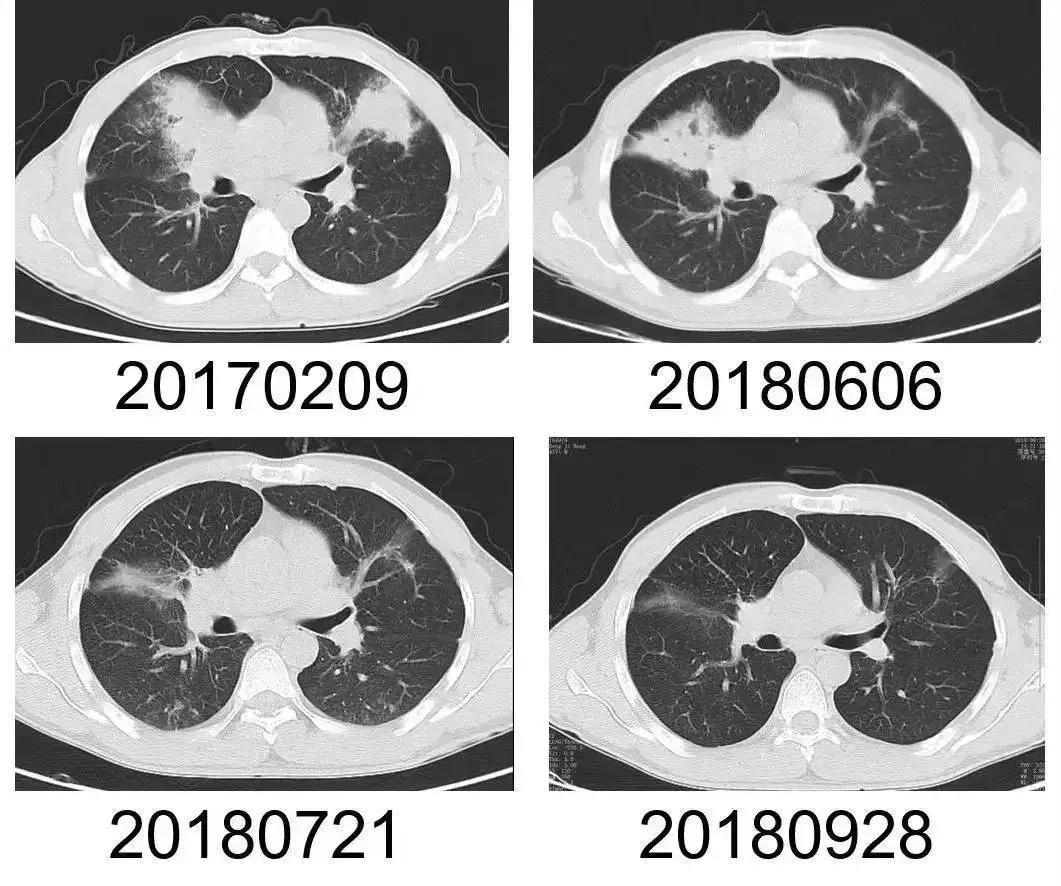

李先生的肺部CT,经对症治疗后,肺部感染灶明显缩小